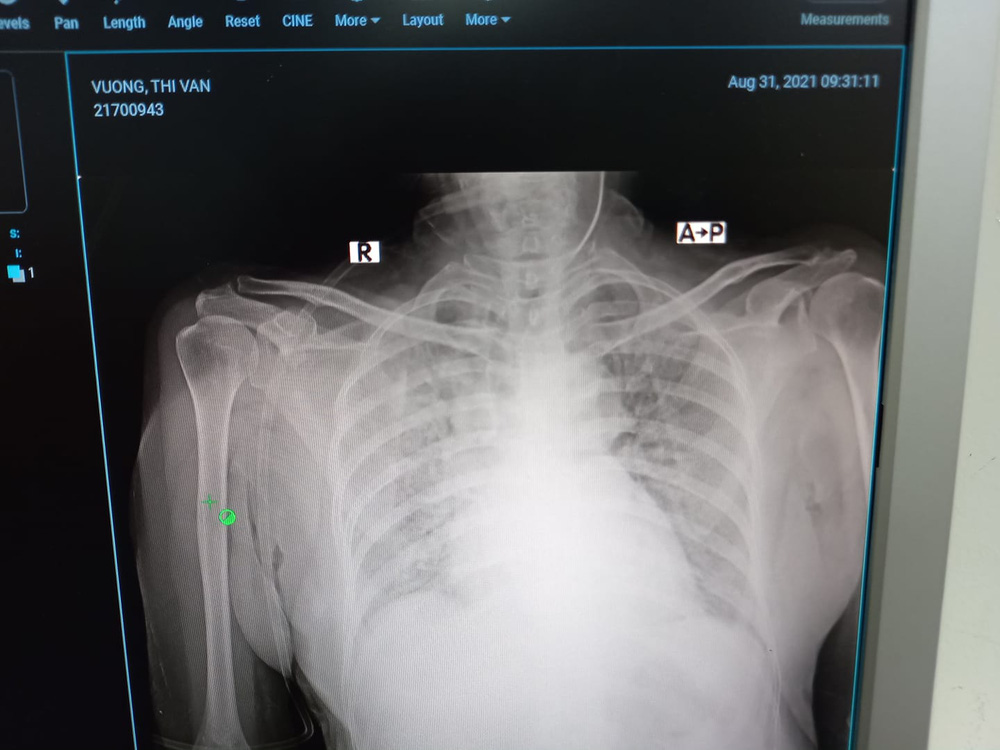

Ca bệnh đặc biệt này thật bất ngờ vì ngay khi nhận buồng mọi người đã bảo, ca này nặng đấy nhé, tràn khí trung thất, tràn khí dưới da. Tức là bệnh nhân này đã bị Covid-19 ăn thủng phổi, nếu trong mấy ngày tới có nặng lên thì cũng không thở máy được, vì đang tràn khí màng phổi. Như vậy khả năng tử vong gần như chắc chắn.

Nhưng thật lòng, bác sĩ Dân thấy anh khó qua khỏi. Xét nghiệm thì thấy các chỉ số của bão cytokin đang hoành hành dữ dội. Hai lá phổi viêm trắng xóa. Bác sĩ phải dùng tối đa oxy hỗ trợ: thở oxy dòng cao HFNC 60 lít/phút, rồi lại chụp thêm ra ngoài một cái mask oxy 15 lít phút. Oxy phun ào ào như thác lũ nhưng phổi viêm nặng như thế, oxycũng không vào máu.

Phổi của bệnh nhân trắng xoá.

BS Dân cho biết buổi chiều 3/9, bác sĩ đưa bệnh nhân chụp cắt lớp CT phổi. Nhìn phổi của bệnh nhân đông đặc gần hết chỉ còn một chút phổi lành, nhưng bệnh nhân đã cai oxy dòng cao được. BS Dân cho biết đây là điều thật là kỳ diệu.